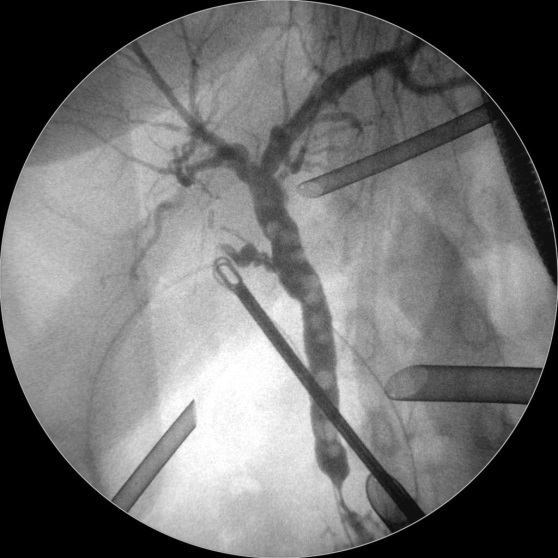

• ERCP = Endoskopisch retrograde Cholangiopankreatikographie: Sollten sich Steine im Gallengang (Choledocholithiasis) bestätigen, müssen diese Steine durch eine Spiegelung (endoskopisch) des Magens bzw. bis zum Eingang des Gallenganges in das Duodenum durch die Kolleginnen und Kollegen der Gastroenterologie entfernt werden.

Bild links: Cholangiographie: Mit Hilfe eines Bildverstärkers wird Kontrastmittel in den Gallengang injiziert, um die Gallengangsteine und Gallengangsanatomie darzustellen.